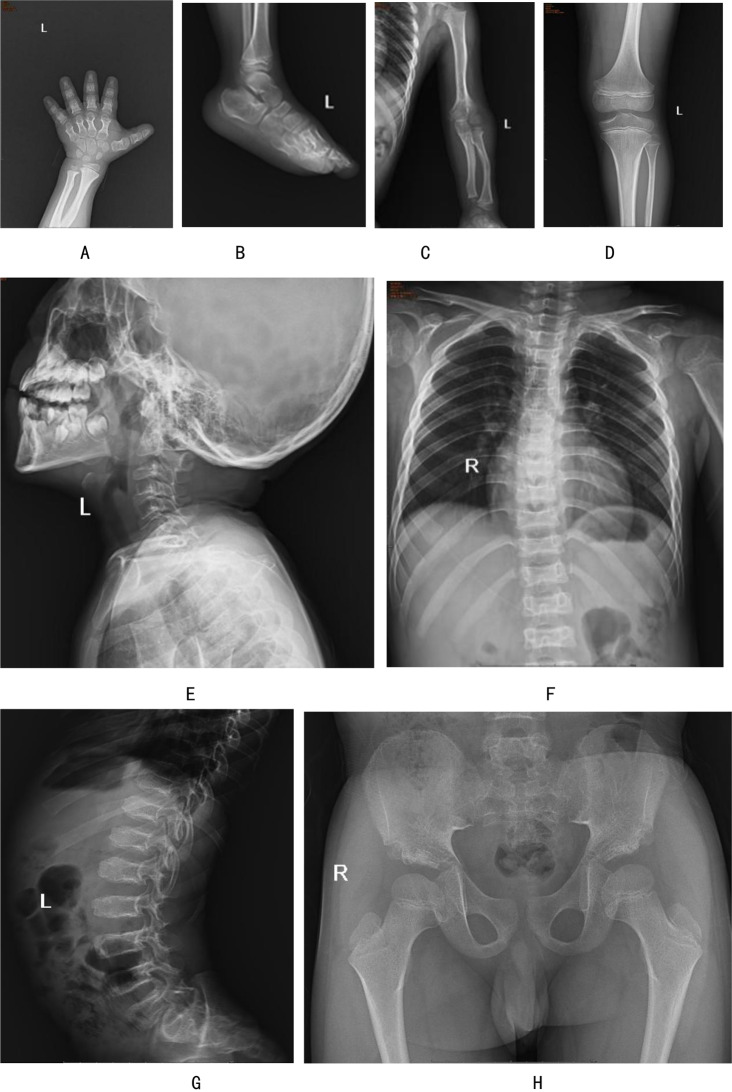

Background: Acromesomelic dysplasia Maroteaux type (AMDM) is a rare autosomal recessive skeletal dysplasia with an estimated prevalence of 1:1,000,000. It is characterized by extreme shortening of the forelimbs and disproportionate short stature.

Case presentation: Here we present the clinical and genetic features of an 8-year-8-month-old boy exhibiting idiopathic short stature and abnormal changes of the appendicular skeleton and axial skeleton, consistent with the established phenotypic spectrum of AMDM. Using diagnostic exome sequencing, we identified two variants in NPR2: a known pathogenic nonsense variant, C.2965 C > T (p.Arg989*), and a missense variant of unknown significance, C.2291T > C (p.Leu764Pro), which has never been reported before. Sanger sequencing confirmed that the variants were inherited from his phenotypically normal parents. The proband is compound heterozygous, while both parents are heterozygous carriers, indicating an autosomal recessive pattern of inheritance.

Conclusion: This study enriches the pathogenic gene mutation spectrum of NPR2 in patients with AMDM and further emphasizes the application of molecular genetic detection in the diagnosis of rare skeletal abnormalities.